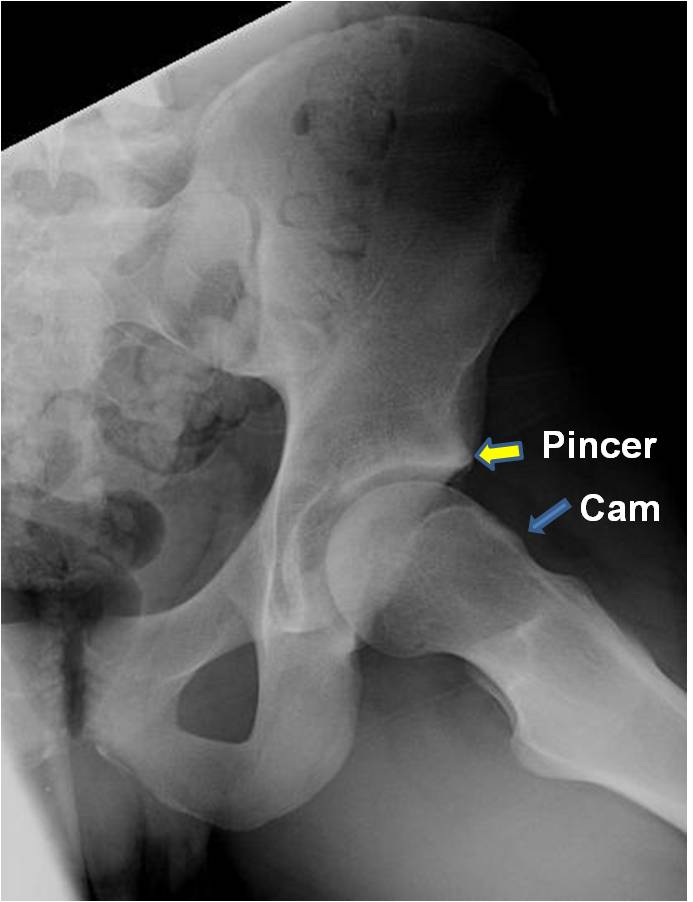

FAI results from abnormal contact between the femoral head and the acetabulum, leading to labral and cartilage damage. It manifests in two primary forms:

- Cam Impingement:

Abnormal shape of the femoral head, reducing clearance.

- Pincer Impingement:

Over-coverage of the femoral head by the acetabulum.

Patients with FAI typically report groin pain exacerbated by flexion activities and prolonged sitting. Diagnostic imaging, including MRI and CT scans, allows for detailed visualization of bony and soft tissue changes, supporting precise diagnosis and treatment planning.